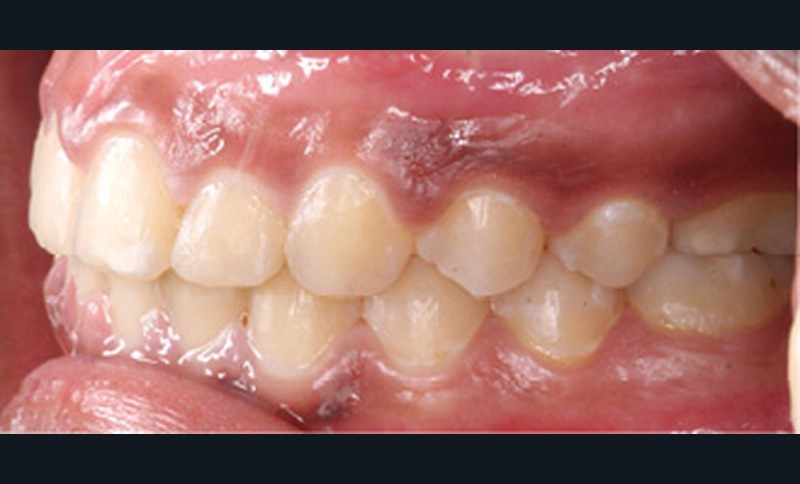

Examen clinique (fig. 1a-h)

À l’examen de face, Anisa présente un visage ovalaire, des hémifaces symétriques, des lignes horizontales parallèles, une augmentation de l’étage inférieur, une occlusion labiale légèrement forcée et des dents mandibulaires exposées au sourire. Les profils général et sous-nasal sont concaves avec un angle naso-labial augmenté et une prochéilie inférieure.

L’examen clinique endo-buccal révèle une denture adulte jeune avec un inversé d’articulé antérieur de 13 à 23, des tatouages gingivaux ethniques et des taches de décalcifications, un parodonte sain mais un brossage insuffisant.

L’arcade maxillaire est en V et la voûte palatine profonde. L’arcade mandibulaire a une forme en U (non-concordance des formes d’arcade) et présente des malpositions des dents cuspidées. La médiane mandibulaire est décalée à gauche de 2 mm ; le recouvrement antérieur est de 2 mm ; les molaires sont en classe III avec un surplomb inversé.